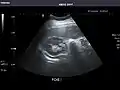

Kidneys: Right and left kidneys measure 11.5 cm and 12 cm in length respectively. No hydronephrosis. Small left lower pole kidney cyst.

Right kidney

Left kidney